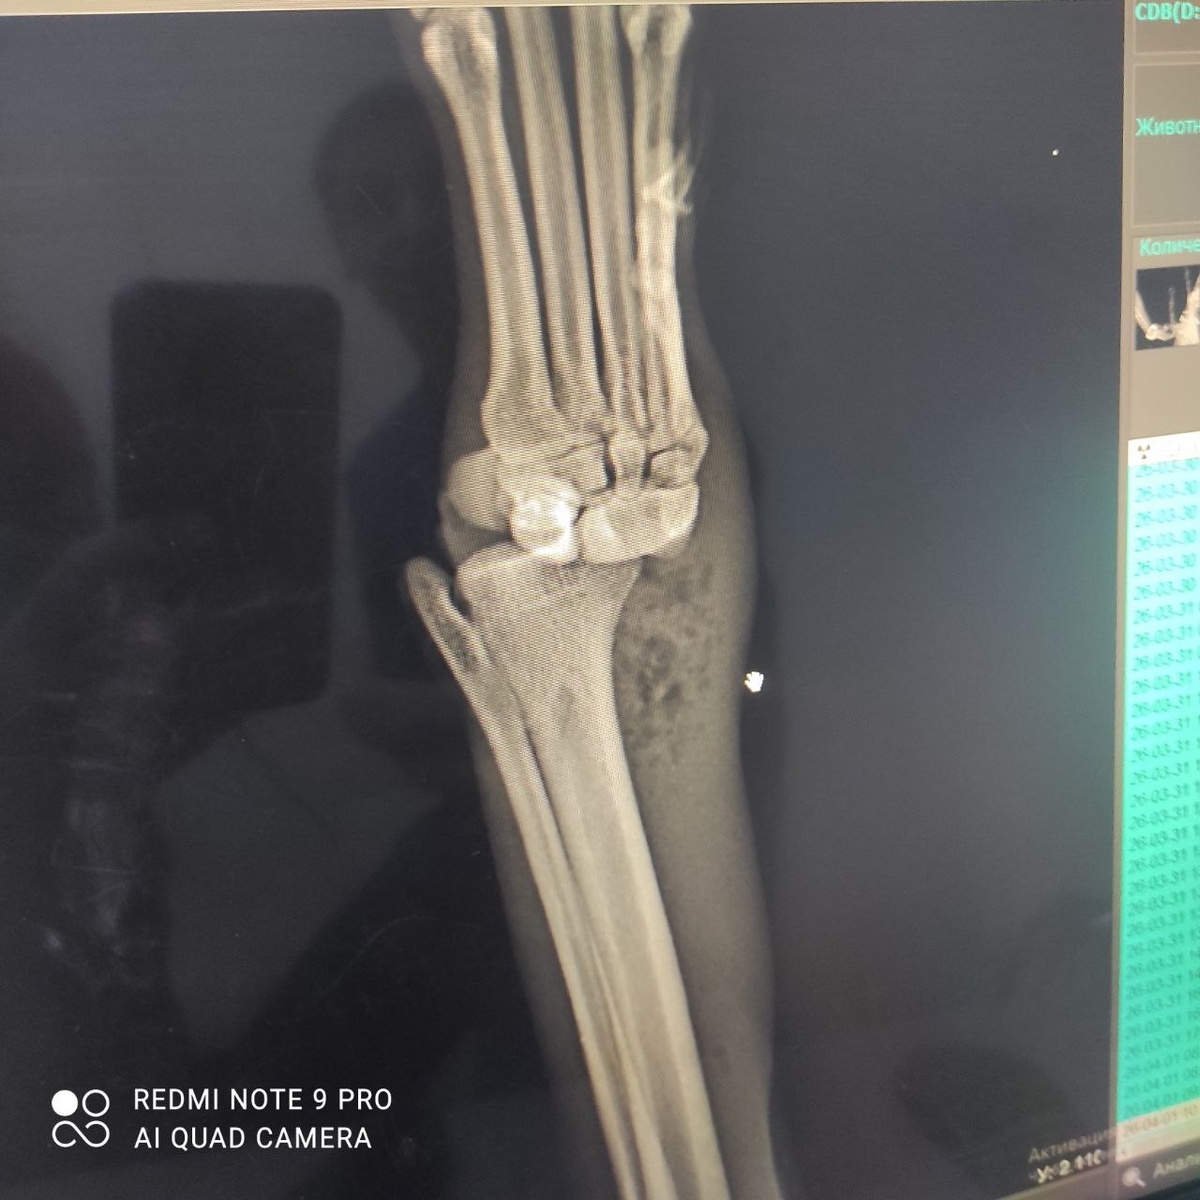

Глашенька очень просит помощи в оплате ее операции...Сегодня собрали лапку,ждём как будет сростаться...Открытый перелом ,инфицирование

сустава- шансы конечно 50/50...

Глашенька очень просит помощи в оплате ее операции...Сегодня собрали лапку,ждём как будет сростаться...Открытый перелом ,инфицирование сустава- шансы конечно 50/50...